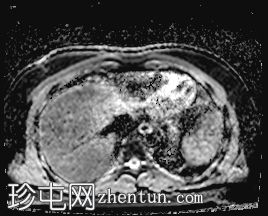

冠状位

T2加权像

T1低信号,T2低信号为主的脾脏肿块,内部可见T2高信号分隔,呈进行性强化。肿块中央可见星状瘢痕。

脾脏硬化性血管瘤样结节性转化(SANT),9.8 cm肿块

顾名思义,脾脏硬化性血管瘤样结节性转化(SANT)是一种纤维性血管病变。本病例展示了SANT的一些典型影像学特征,包括边界清晰的病灶,中央可见瘢痕,以及呈放射状进行性强化。这些特征使得术前MRI诊断较为明确。尽管SANT是一种良性病变,但大多数患者仍需行脾切除术以明确病理诊断。